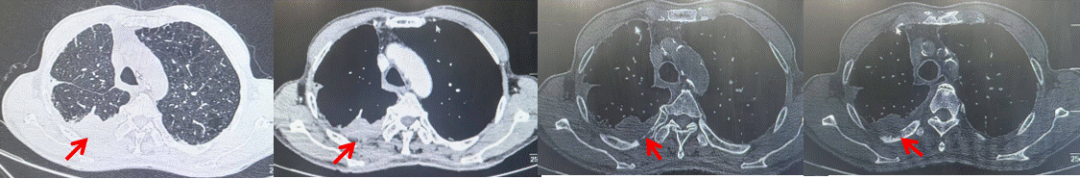

2024.09.12复查胸部CT示左侧胸膜结节,大者约为27mmx13mm,考虑转移可能性大,纵隔淋巴结增大,恶性?(如图6)。患者行胸膜穿刺活检取病理,结果示(胸膜)结合免疫组化,支持鳞状细胞癌,PD-L1(克隆号28-8)TPS约20%。分期为rT0N2bM1a IVA期,DFS为10个月。2024.09.24起行替雷利珠单抗联合紫杉醇+卡铂方案治疗4周期,复查胸CT评效SD(如图7)。后患者因脑梗塞停止治疗,于综合医院就诊,后未返院复查及治疗。

图6:患者胸膜及纵隔转移(2024.09)胸部CT肺窗及纵隔窗

图7:替雷利珠单抗联合白蛋白紫杉醇+卡铂治疗4周期后(2024.12)胸部CT肺窗及纵隔窗